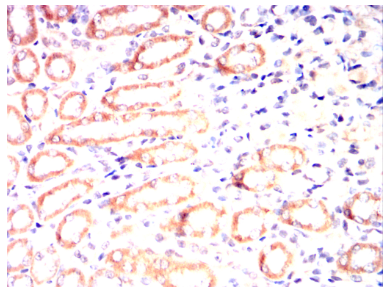

ALPL Mouse Monoclonal antibody[2F4D11]

IHC    1/200 - 1/1000